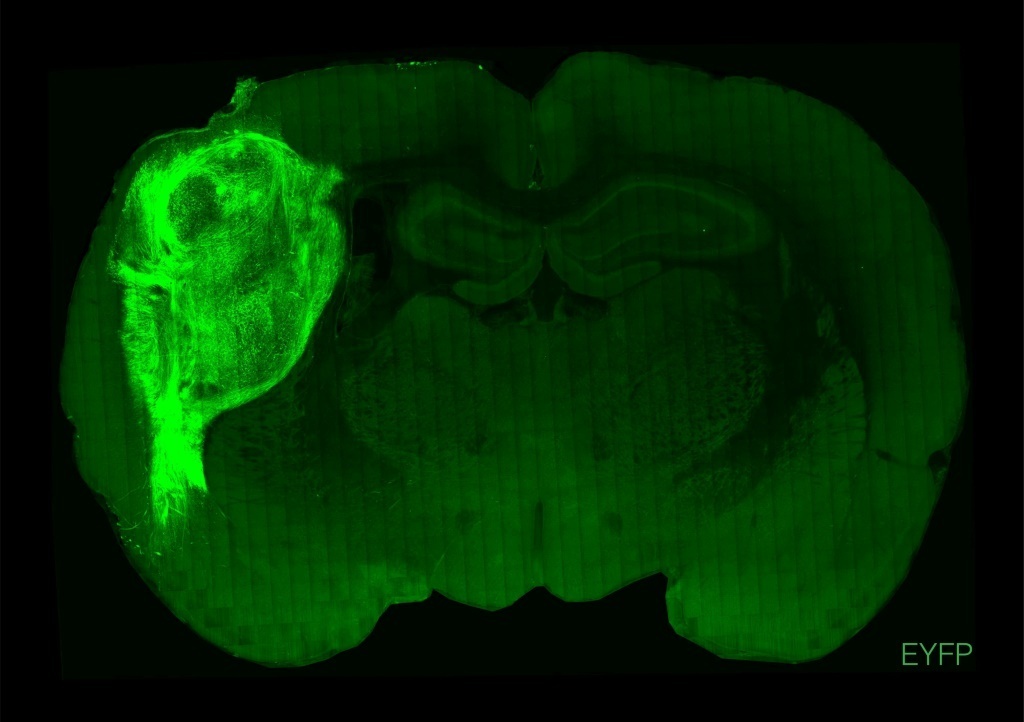

"By transplanting them at these early stages, we found that these organoids can grow relatively large, they become vascularised (receive nutrients) by the rat, and they can cover about a third of a rat's (brain) hemisphere," Pasca said.

To test how well the human neurons integrated with the rat brains and bodies, air was puffed across the animals' whiskers, which prompted electrical activity in the human neurons.

That showed an input connection -- external stimulation of the rat's body was processed by the human tissue in the brain.

The scientists then tested the reverse: could the human neurons send signals back to the rat's body?

They implanted human brain cells altered to respond to blue light, and then trained the rats to expect a "reward" of water from a spout when blue light shone on the neurons via a cable in the animals' skulls.

After two weeks, pulsing the blue light sent the rats scrambling to the spout, according to the research published Wednesday in the journal Nature.